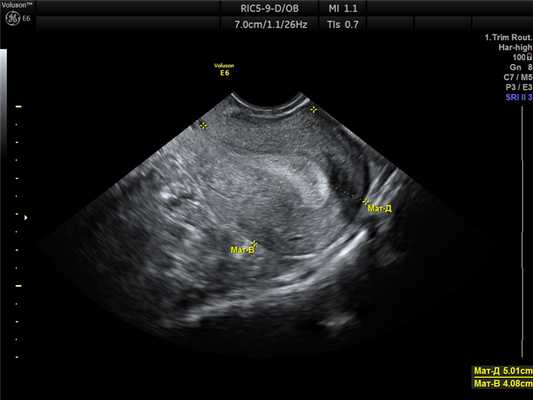

Маточная беременность малого срока

Рис. 3. Маточная беременность 7-8 недель.

Размеры плодного яйца и эмбриона соответствуют сроку задержки менструации.

При беременности в полости матки визуализируется на ранних сроках только плодное яйцо, в дальнейшем, появляется эмбрион. Размеры плодного яйца и эмбриона должны соответствовать сроку беременности по менструации.

Обязательной является также и оценка сердцебиения у плода, которое, как правило, появляется уже после 10-14 дней задержки менструации.

При беременности в одном из яичников должно визуализироваться желтое тело беременности, которое контролирует развитие данной беременности и обеспечивает на ранних сроках (до формирования плаценты) жизнедеятельность плода.